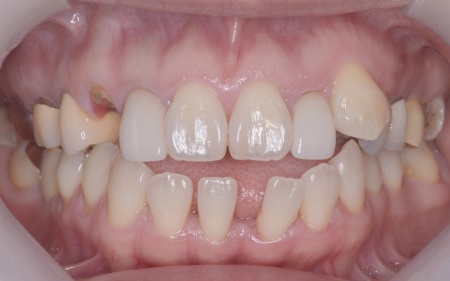

| 相談内容 | 「左下の奥歯が欠けたのと、右上の差し歯が取れた」とご相談いただきました。 |

| カウンセリング | 拝見したところ、左下と右上の歯はともに大きな虫歯があり、歯だけでなく被せ物を支える土台の部分にも影響が及んでいました。

さらに、ほかの歯に入っている詰め物や被せ物の周囲にも、過去に治療した部分に再び虫歯ができる二次カリエスが複数見つかりました。 また、噛み合わせを確認したところ、奥歯で噛み合わせた際に上下の前歯が当たらず隙間ができる開咬(かいこう)が認められました。 実際に患者様の場合も、特定の歯に長期間強い力がかかり続けたことで歯や修復物の破損、さらには口腔内全体のトラブルにつながった可能性が高いと考えられました。 修復治療が必要でしたがこの噛み合わせの問題を改善しないまま行うと、治療した歯に再び過度な力が加わって被せ物の破損・脱離や虫歯の再発を招くリスクが高まります。 |